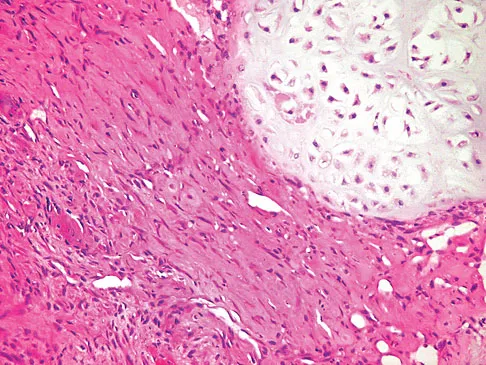

Figures 12a through 12e show the radiograph, MRI scans, and biopsy specimens of a 17-year-old boy. What is the most likely diagnosis?

The images show an epiphyseal lesion. The MRI scan shows extensive bone edema surrounding the lesion, consistent with chondroblastoma. Histology shows polygonal chondroblasts in a cobblestone-like pattern and areas of calcification consistent with chondroblastoma. Although some giant cells are seen, the age of the patient and the polygonal chondroblasts differentiate this lesion from giant cell tumor. Clear cell chondrosarcoma is an epiphyseal lesion that occurs in an older population, and the cells have clear cytoplasm. This lesion is not producing bone on imaging or histologic specimen, eliminating osteosarcoma. Tuberculous septic arthritis can be an epiphyseal lesion, but granulomas would be seen on histology. Menendez LR (ed): Orthopaedic Knowledge Update: Musculoskeletal Tumors. Rosemont, IL, American Academy of Orthopaedic Surgeons, 2002, pp 103-111.